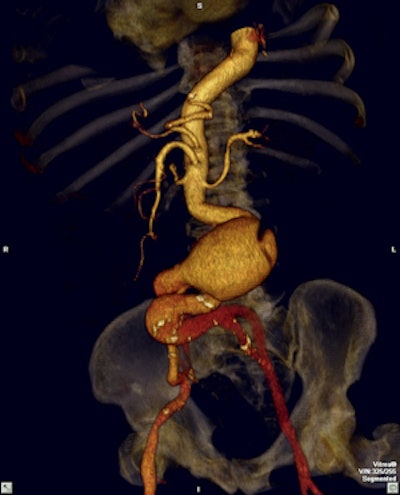

Leading hospitals in Colombia make use of the latest software to visualize and analyze 2D, 3D, and 4D images. All images courtesy of the Asociación Colombiana de Radiología.However, in today's ever-changing world with the discovery of novel techniques and technologies and new forms of practice and care models, there is an underlying concern about what this could mean for the future of the practice of radiology.